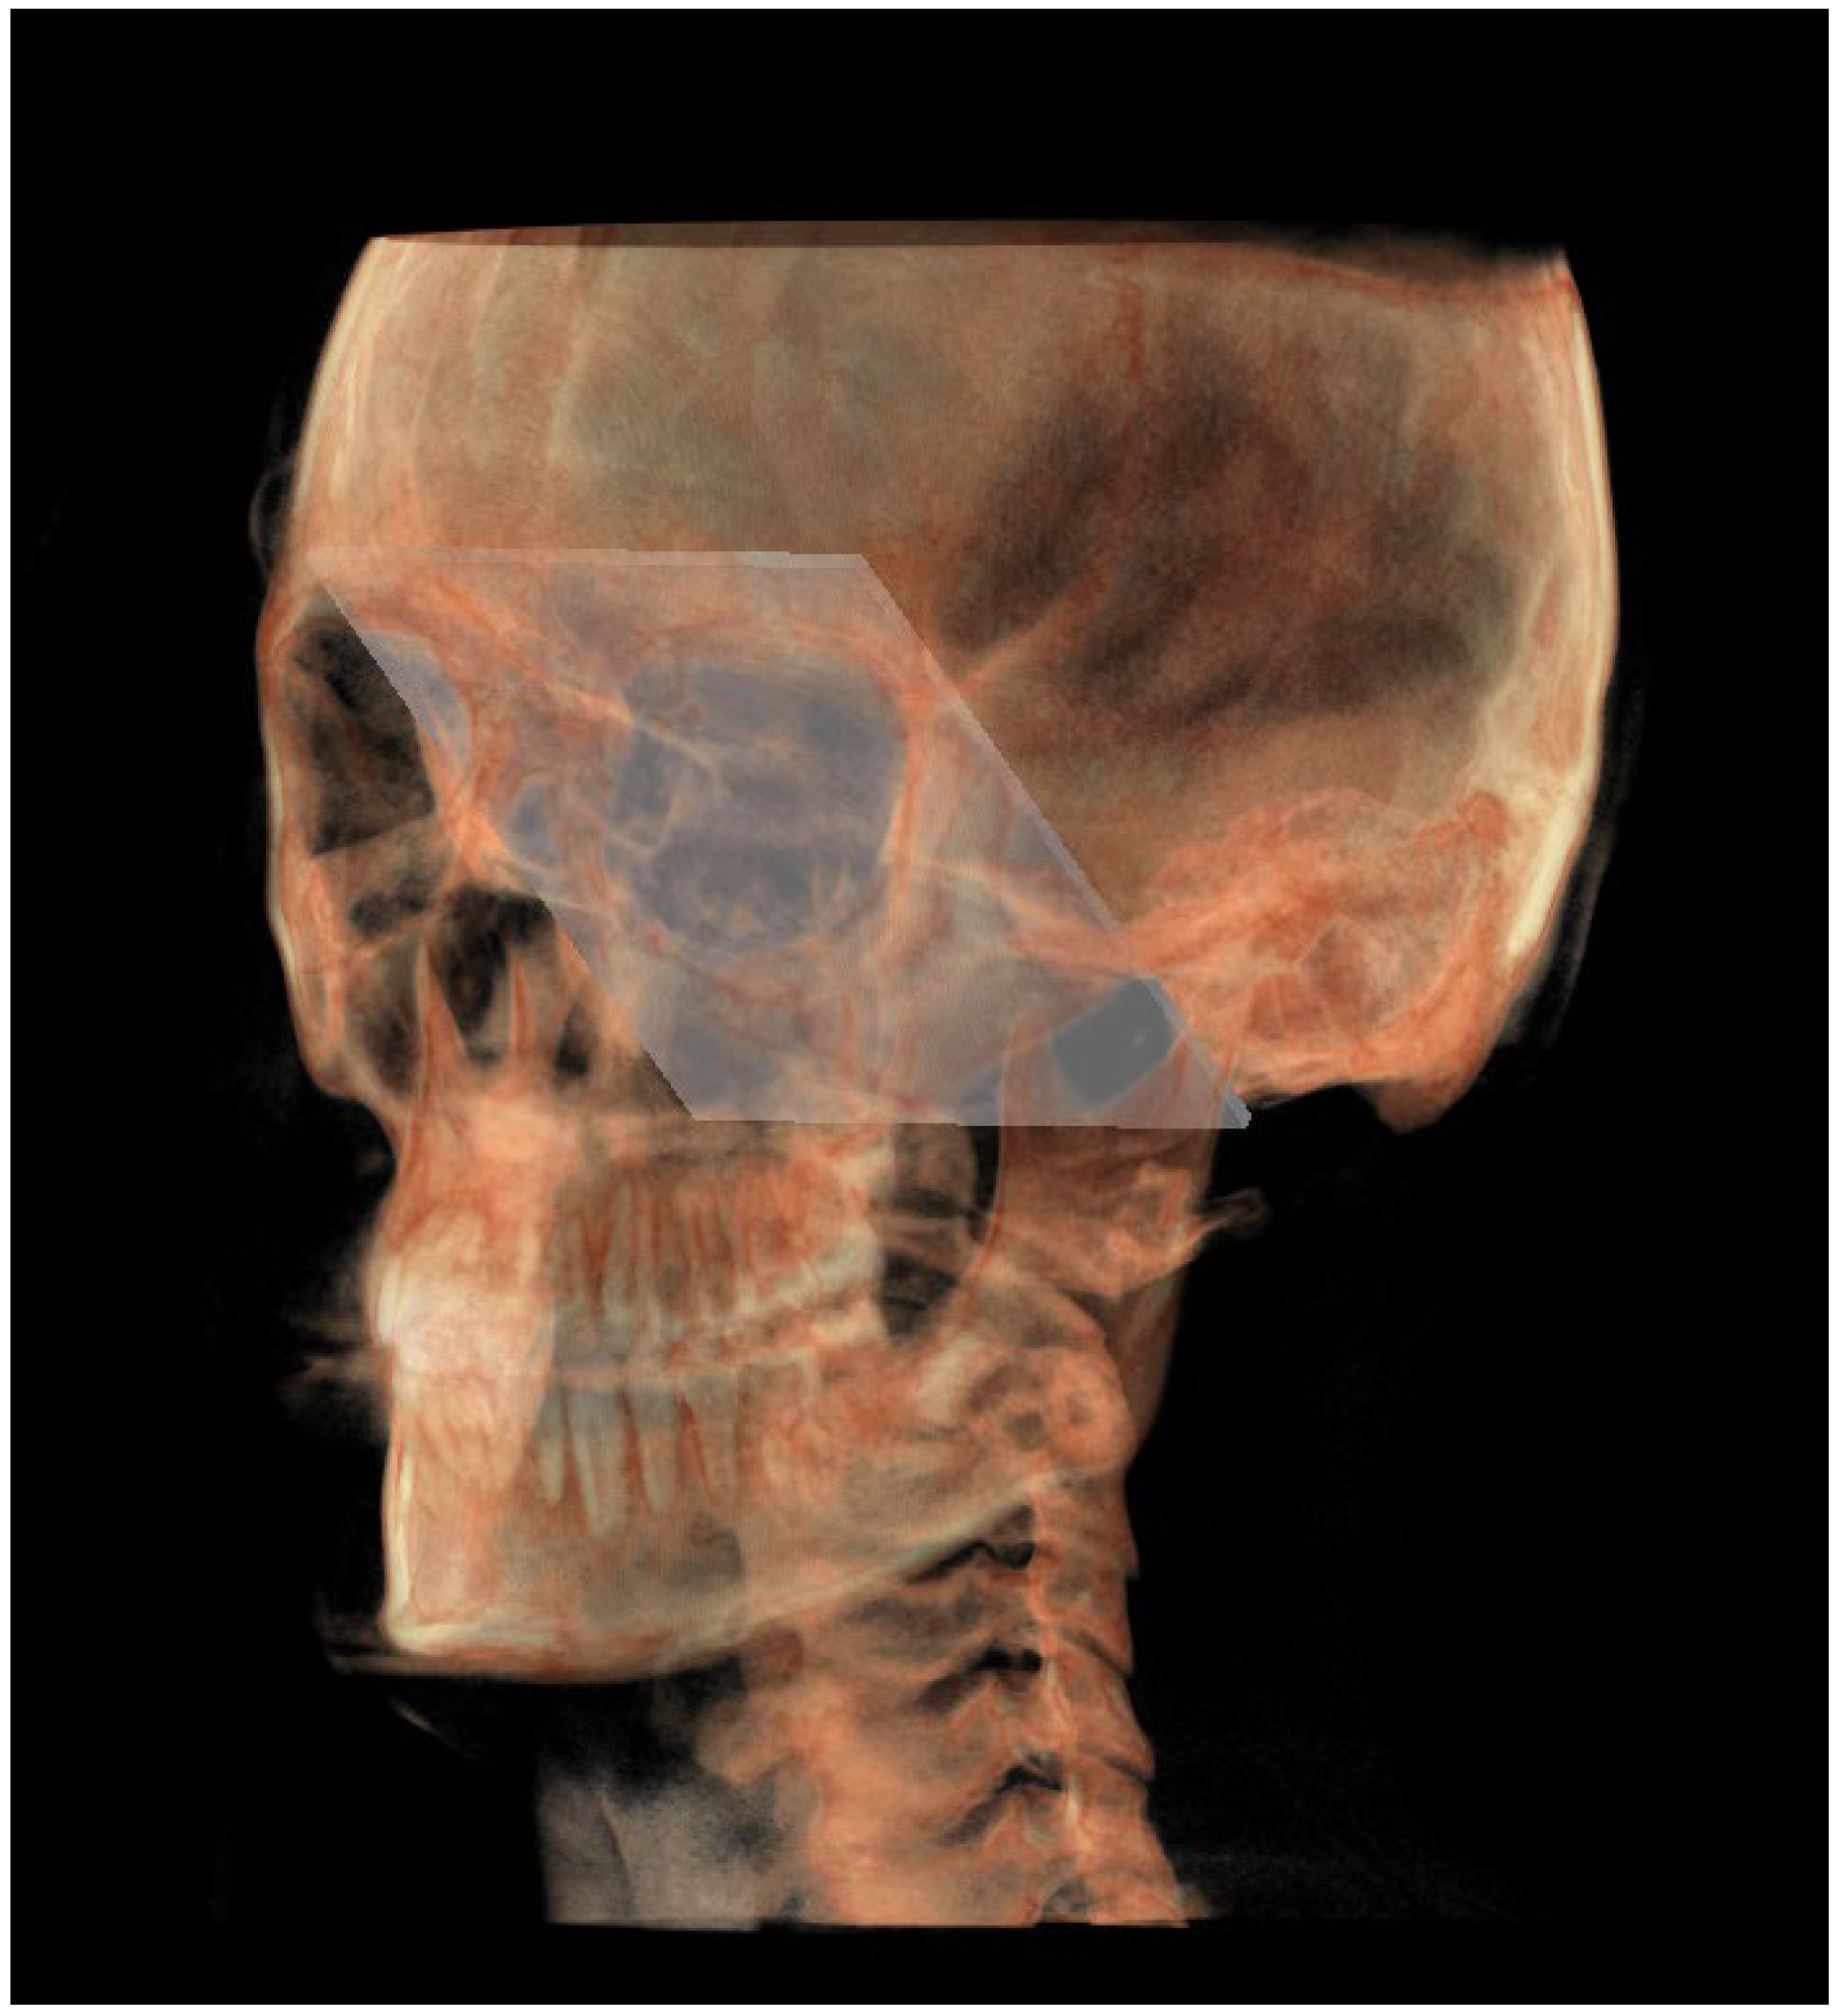

| Middle cranial floor, right side (rMCF) | Point in superior and endocranial surface where greater wings of sphenoid cross anterior cranial floor at posterolateral bony wall of right orbit | Anterior-most point of middle cranial floor (endocranial surface of greater wings of the sphenoid), right side | Point in endocranial surface where greater wing of sphenoid crosses anterior cranial floor at lateral bony wall of right orbit |

| Middle cranial floor, left side (lMCF) | Point in superior and endocranial surface where greater wings of sphenoid cross anterior cranial floor at posterolateral bony wall of left orbit | Anterior-most point of middle cranial floor (endocranial surface of greater wings of the sphenoid), left side | Point in endocranial surface where greater wing of sphenoid crosses anterior cranial floor at lateral bony wall of left orbit |